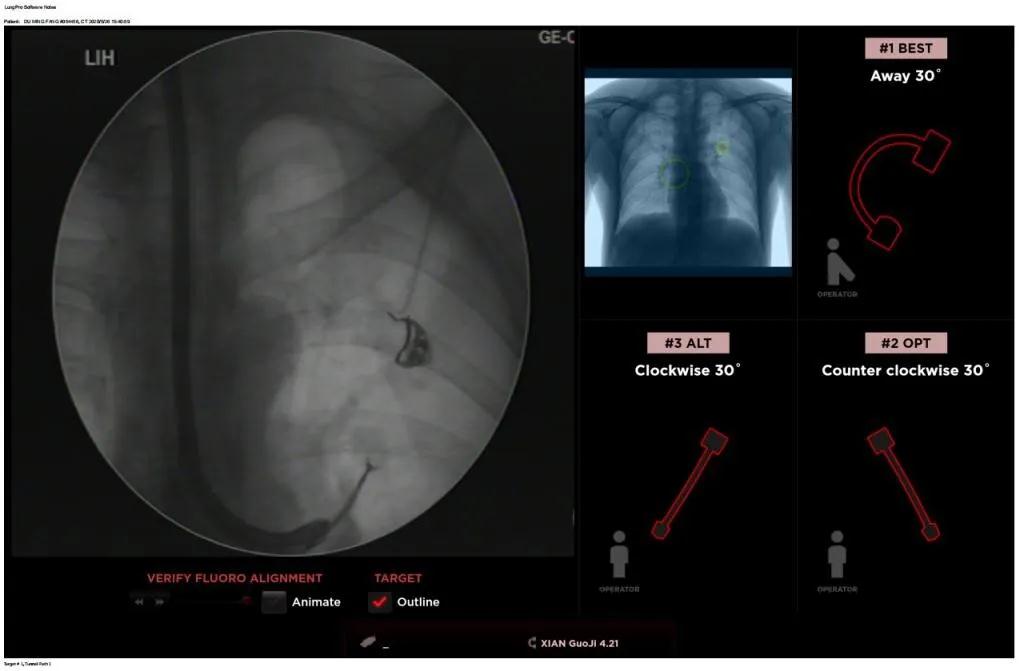

經(jīng)過充分的討論后,歐陽海峰副院長決定為患者實施LungPro全肺導(dǎo)航系統(tǒng)引導(dǎo)的經(jīng)支氣管跨肺實質(zhì)肺外周結(jié)節(jié)活檢術(shù)。Broncus導(dǎo)航系統(tǒng)LungPro具有全球領(lǐng)先獨創(chuàng)的BTPNA技術(shù)(支氣管鏡下跨結(jié)節(jié)抵達(dá)術(shù)),可以實現(xiàn)對氣道外周孤立性肺小結(jié)節(jié)的精準(zhǔn)定位,建立直接通往氣道外病變部位的通道,以實現(xiàn)全肺的診斷及后續(xù)治療。這項技術(shù)不僅彌補了現(xiàn)有支氣管鏡技術(shù)由于受限于病變部位是否有氣道可通向以及無法準(zhǔn)確定位病變部位而造成的較低診斷率,同時還彌補了CT引導(dǎo)下經(jīng)胸穿刺(TTNA)無法適用于某些特定部位如中央及肩胛骨等結(jié)節(jié)的問題,并且還避免了經(jīng)胸穿刺給患者帶來氣胸、出血的高風(fēng)險,可有效提高肺部結(jié)節(jié)及早期肺癌診斷陽性率,亦可用于早期肺癌的射頻消融或微波治療,具有微創(chuàng)、安全、同期雙肺診療等優(yōu)勢。